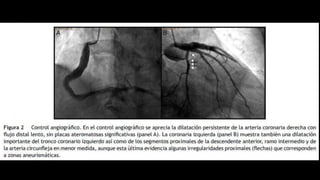

•angiografía

ANGIOGRÁFICAS